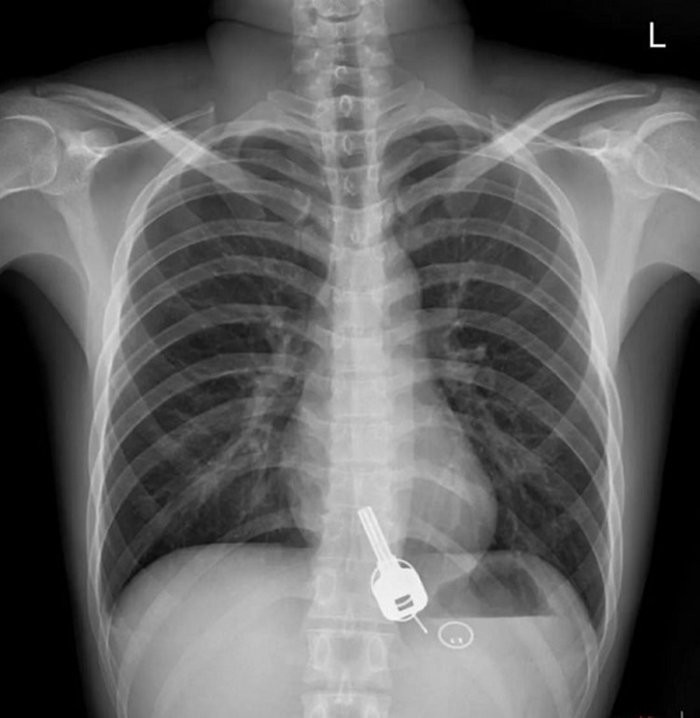

Sáng hôm sau tỉnh rượu, anh cảm thấy cơn đau nhói ở ngực, nên đến bệnh viện khám. Kết quả chụp X-quang phát hiện dị vật giống như chìa khóa nằm trong thực quản bệnh nhân.

Phim chụp X-quang chìa khóa trong thực quản bệnh nhân. (Ảnh: Sohu)

Sau khi phân tích, các bác sĩ nhận thấy nếu để chiếc chìa khóa đi qua hệ tiêu hóa và ra ngoài theo cách tự nhiên thì quá nguy hiểm vì có thể cào rách ruột hoặc gây tắc nghẽn ruột. Các bác sĩ thử dùng thiết bị nội soi để lấy chìa khóa ra ngoài, nhưng kế hoạch thất bại do kích thước chìa khóa lớn nên không thể đi qua phần hẹp nhất của thực quản nằm gần cổ họng.